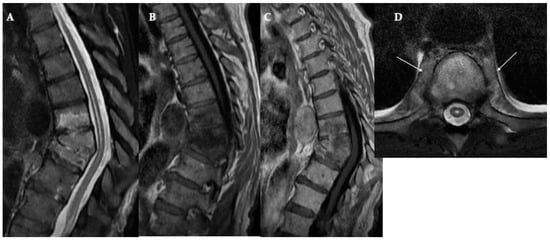

8.1. Modic Type I Degeneration